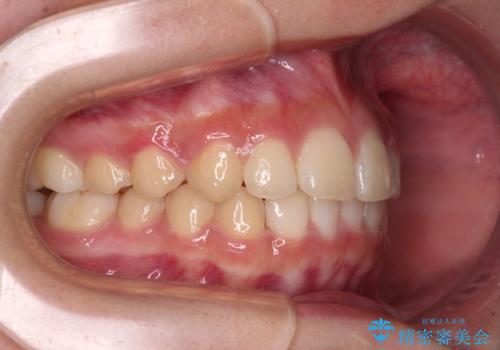

ワイヤー装置と補助装置を有効に活用し、さらには高校生ということもあり、1年9か月で狙い通りの仕上がりを達成することができました。

奥歯の咬み合わせと深い咬み合わせを改善した後、インビザラインで歯列を整えることとしました。